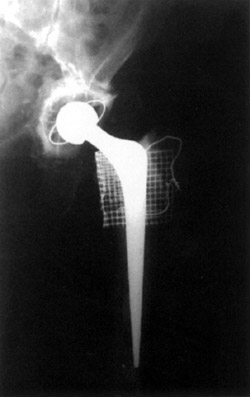

1. 2.

Figure 1. Third time revision of femoral stem.

This patient was referred for a third time revision of his left THR fractured stem and fracture shaft of femur.

Open reduction and internal fixation left femur, with strut allograft and Dall-Miles cables. Revision total hip replacement to impaction grafted long stem Exeter.